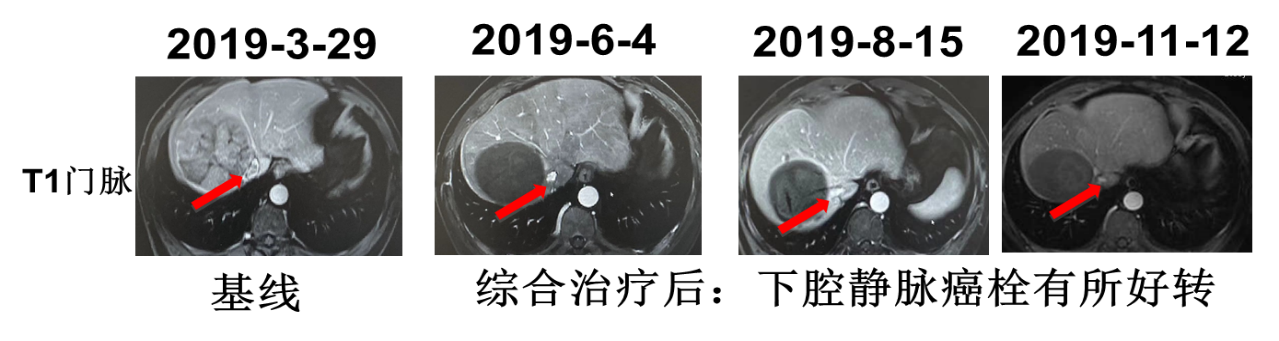

2019年4月2日行TACE+肝肿瘤微波消融术,5月6日起予以信迪利单抗治疗(200mg q3w ivgtt)联合仑伐替尼(12mg qd po),5月10日复查AFP降为正常(10.3ng/ml),PIVKA-Ⅱ降至3352 mAU/ml。6月4日复查肝脏MRI:mPR,局部强化结节,下腔静脉癌栓较前有所好转。7月2日再次行TACE术。术后于7月8日~9月16日行信迪利单抗注射4周期。8月15日复查MRI:mPR,强化结节好转,下腔静脉癌栓有所好转。8月19日复查PIVKA-Ⅱ进一步降至1202mAU/ml。11月12日复查AFP 12.4ng/ml,PIVKA-Ⅱ 1784mAU/ml,MRI提示病灶稳定。治疗经过见图2。MRI疗效评估见图3、图4、图5。

image005.png

image006.png

图5. MRI疗效评估

患者为中老年男性,既往有乙型病毒性肝炎病史及抽烟史。2019年3月MRI检查发现右肝占位。肿瘤标志物检测结果AFP为418.8ng/mL;PIVKA-Ⅱ:40208mAU/ml,结合患者病史及影像学检查诊断为肝细胞癌。肿瘤的分期对于预后以及治疗方案的制定具有重要的指导作用,肝细胞癌的分期标准比较多,常用的有巴塞罗那(BCLC)分期和TNM分期,本例患者根据巴塞罗那分期定为C期;TNM分期为T4N0M0,IIIB期。患者的体能状态评价根据ECOG标准评分为0分;肝功能化验无明显异常,Child-Pugh 评级为A级。总体来说,患者肝脏病灶局限,无远处转移,并且体能状态以及肝功能良好,于2019年4月2日针对肝脏病灶行TACE+肝肿瘤微波消融术,术后1个月起(5月6日)信迪利单抗联合仑伐替尼治疗,5月10日复查肿瘤标志物明显降低。6月4日复查发现原病灶周边强化结节,于是再次行TACE治疗,术后继续给以信迪利单抗联合仑伐替尼治疗。2019年8月15日复查,MRI显示原病灶强化结节及下腔静脉癌栓有所好转。至11月12日,信迪利单抗治疗已10个周期,复查肿瘤标志物及MRI均提示病灶稳定。